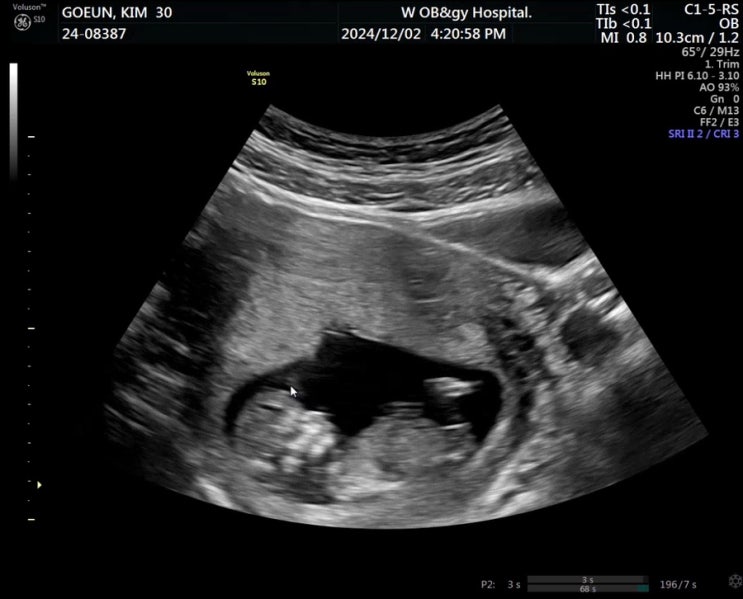

12/1-12/13 임신일기 12주-13주 컨디션 회복과 함께 도파민 찾는중

*** 12-13주차 증상 *** 1. 밤 11시에 취침해도 다음날 컨디션 쏘쏘 이제 컨디션 회복 시작이다~!!!!!! 막 ...